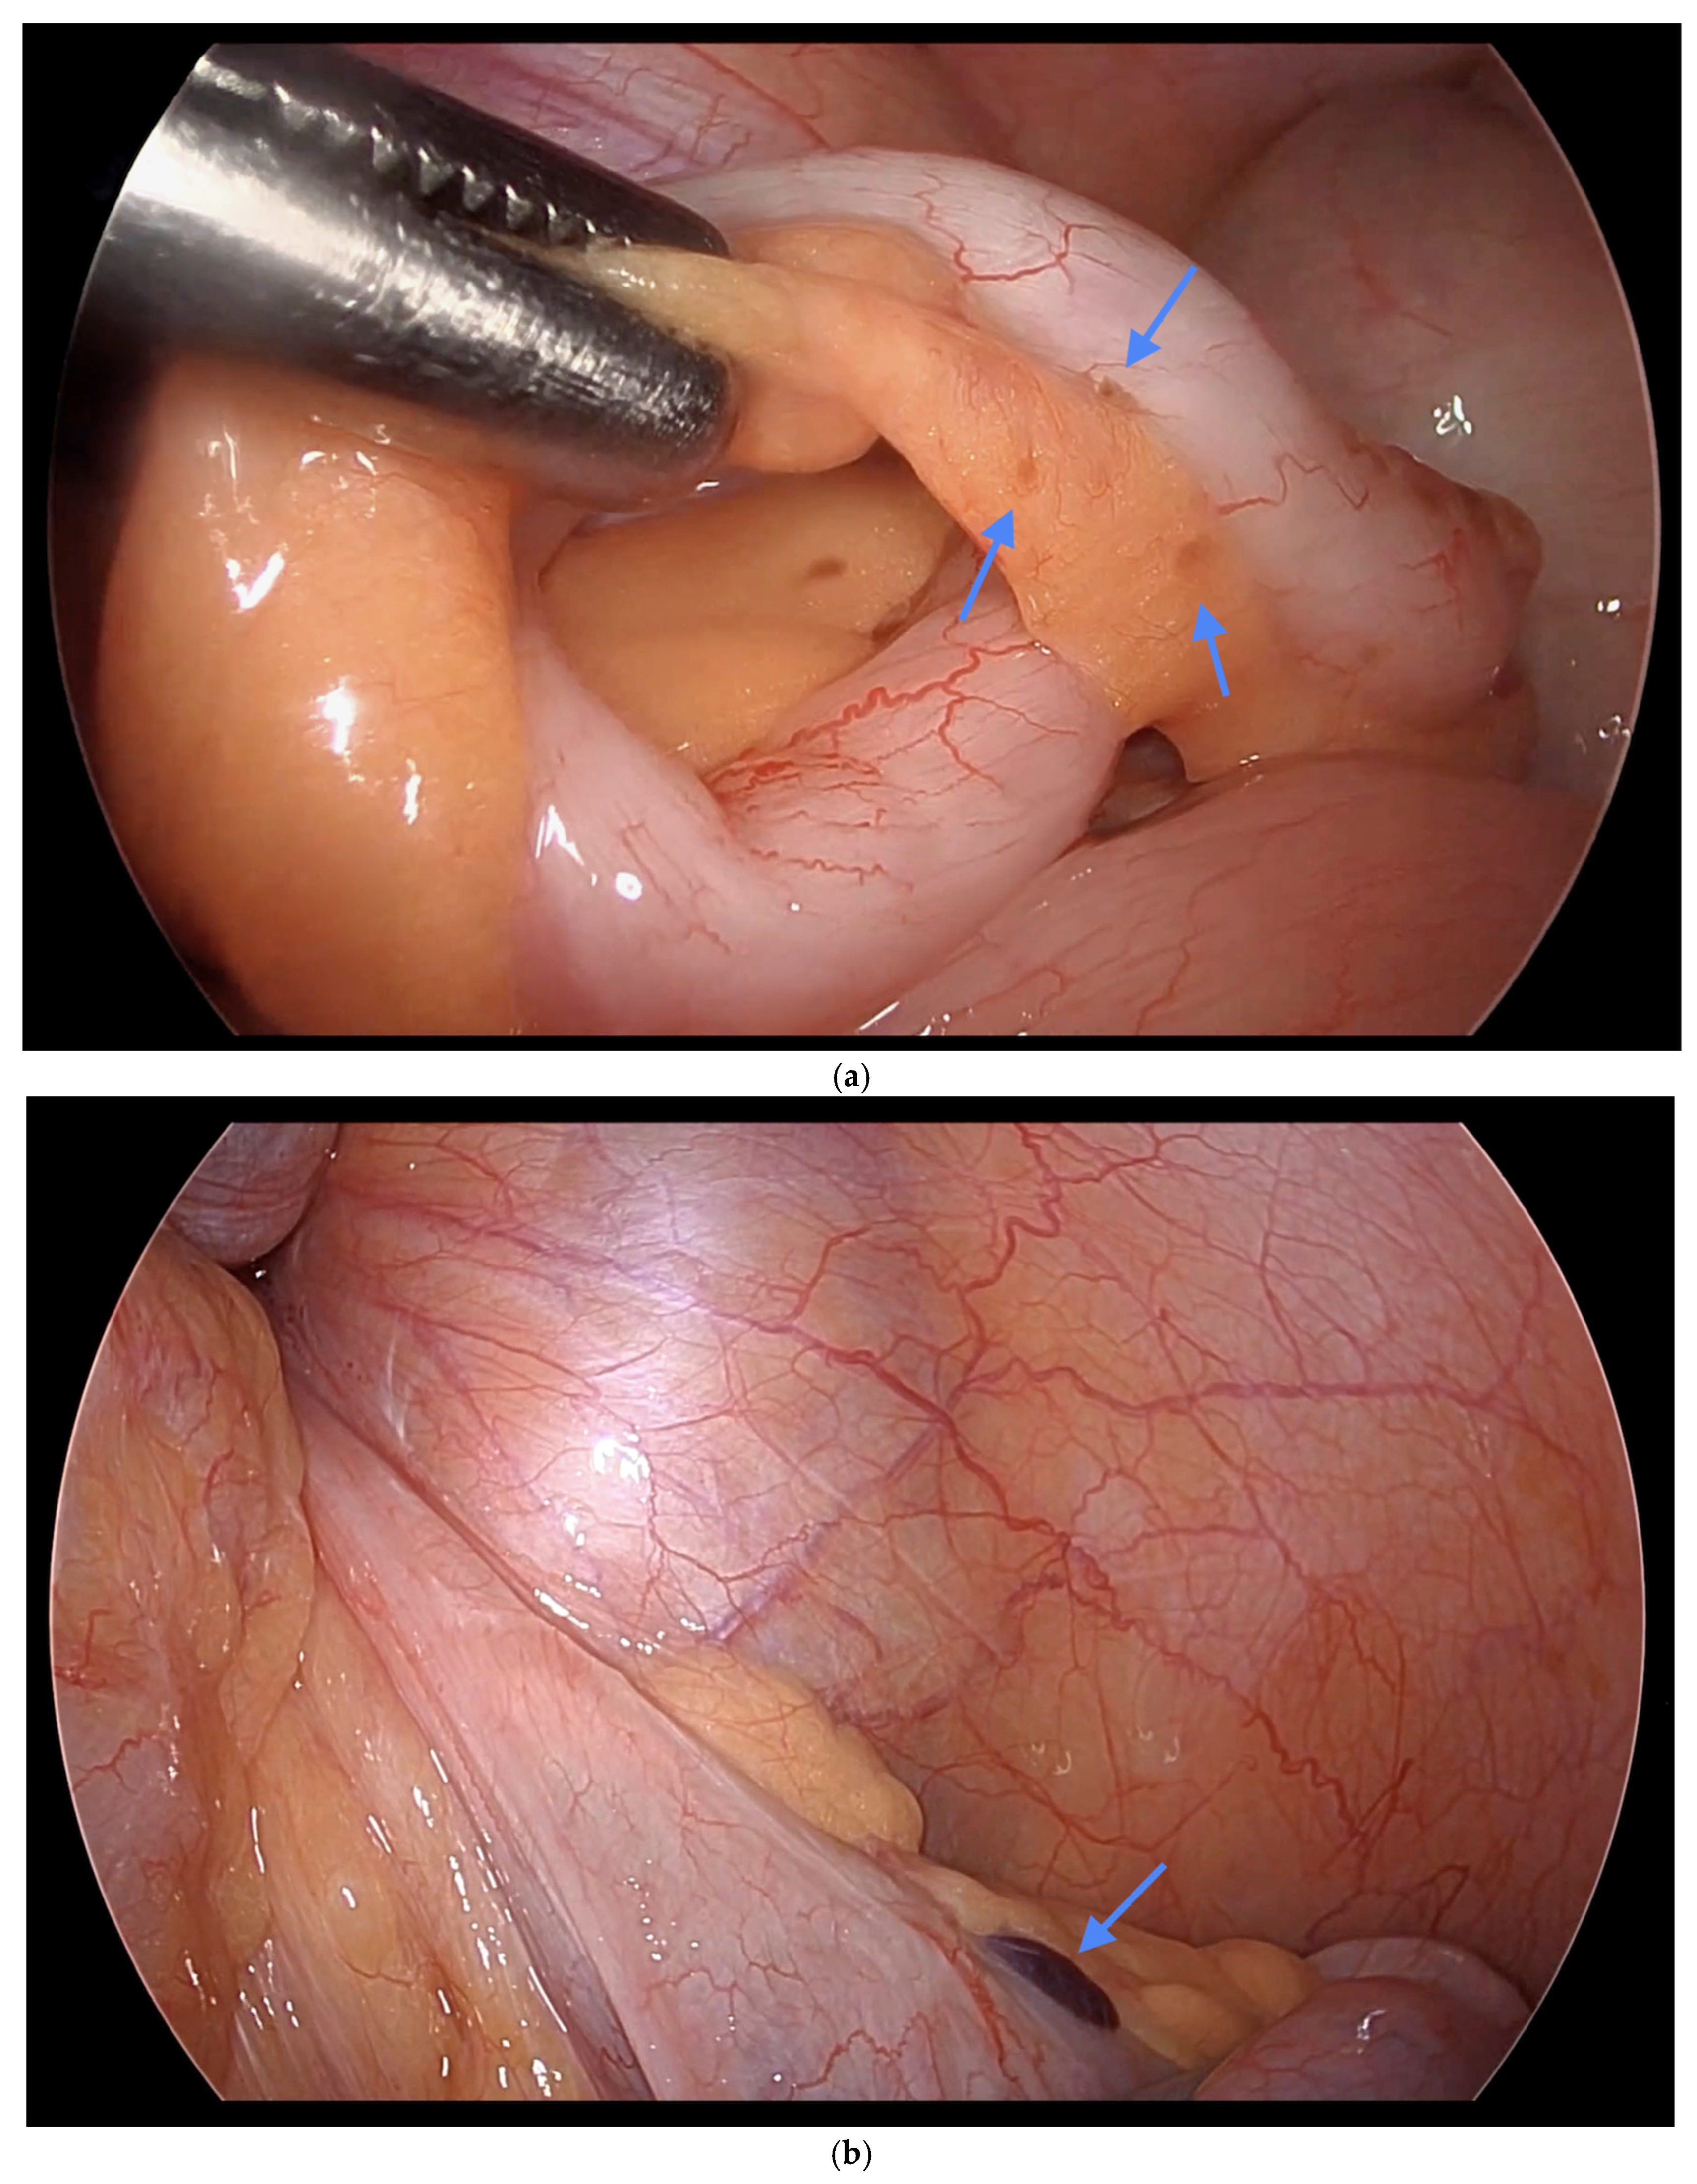

Figure 3. (a) i. Fibrous obliteration, and endometriosis at the tip. ii. Inflammation of the appendix indicating possible acute appendicitis. (b) Endometriosis on the tip of the appendix. Blue arrows indicate (a) (i) fibrous obliteration and endometriosis at the tip of the appendix, and (ii) inflammation suggesting possible acute appendicitis; and (b) endometriosis at the tip of the appendix.

Informed consent was obtained preoperatively, which included a discussion of the possibility of intraoperative appendectomy if appendiceal abnormalities were identified. During surgery, after optimal excision and ablation of endometriotic lesions, the appendix was carefully evaluated for evidence of endometriotic implants, serosal abnormalities, adhesions, fibrous obliteration, or features suggestive of acute or chronic appendicitis (Figure 1, Figure 2 and Figure 3). If abnormal findings were present, intravenous metronidazole was administered for infection prophylaxis, and a laparoscopic appendectomy was performed using the existing port sites [15]. The surgical technique included division of the mesoappendix, followed by transection and closure of the appendiceal base using a vascular stapler. The specimen was placed into a laparoscopic retrieval pouch and sent for histopathologic analysis [15,16].

Among the 216 patients with confirmed appendiceal abnormalities, many presented with more than one pathological finding (Figure 1, Figure 2 and Figure 3). Specifically, 34 patients (14.41%) had histologically confirmed appendiceal endometriosis lesions, 140 patients (59.32%) showed focal or serosal adhesions, 82 (34.75%) demonstrated fibrous obliteration, typically observed as obliteration of the appendiceal tip, and 20 (8.47%) exhibited signs of inflammation. Notably, three cases were diagnosed with neuroendocrine tumors of the appendix: one was confirmed to be malignant, while the other two were benign (Table 2).